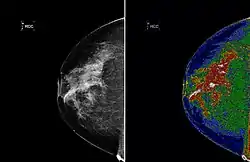

A region of interest (often abbreviated ROI), are samples within a data set identified for a particular purpose.[1] The concept of a ROI is commonly used in many application areas. For example, in medical imaging, the boundaries of a tumor may be defined on an image or in a volume, for the purpose of measuring its size. The endocardial border may be defined on an image, perhaps during different phases of the cardiac cycle, for example, end-systole and end-diastole, for the purpose of assessing cardiac function. In geographical information systems (GIS), a ROI can be taken literally as a polygonal selection from a 2D map. In computer vision and optical character recognition, the ROI defines the borders of an object under consideration. In many applications, symbolic (textual) labels are added to a ROI, to describe its content in a compact manner. Within a ROI may lie individual points of interest (POIs).

Medical imaging standards such as DICOM provide general and application-specific mechanisms to support various use-cases.